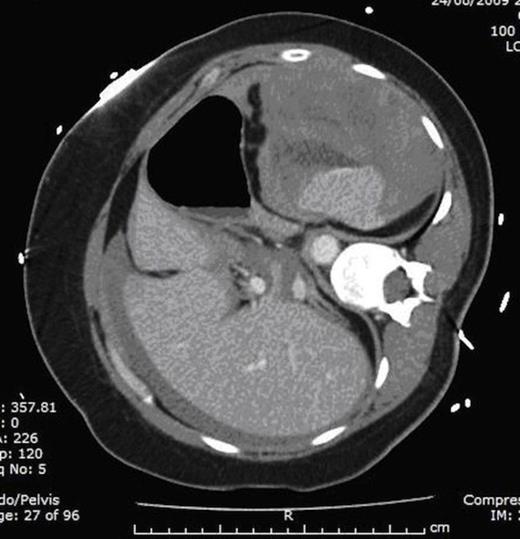

Six hours later, she developed upper abdominal pain. Systolic blood pressure had dropped from 121mmHg to 89mmHg. On examination, she had a tender upper abdomen with associated guarding. Rectal examination revealed soft stool only. ECG had remained improved. Haemoglobin was found to have decreased from 13g/dl to 9g/dl, and therefore the heparin infusion was discontinued and 4 units of packed red blood cells were transfused. A surgical opinion was requested and a Computed Tomography (CT) scan of abdomen and pelvis was performed. CT showed a large haemoperitoneum with a large peri-splenic haematoma (Fig. 1).

Computed Tomography (CT) of abdomen and pelvis scan demonstrating large haemoperitoneum with a large peri-splenic haematoma